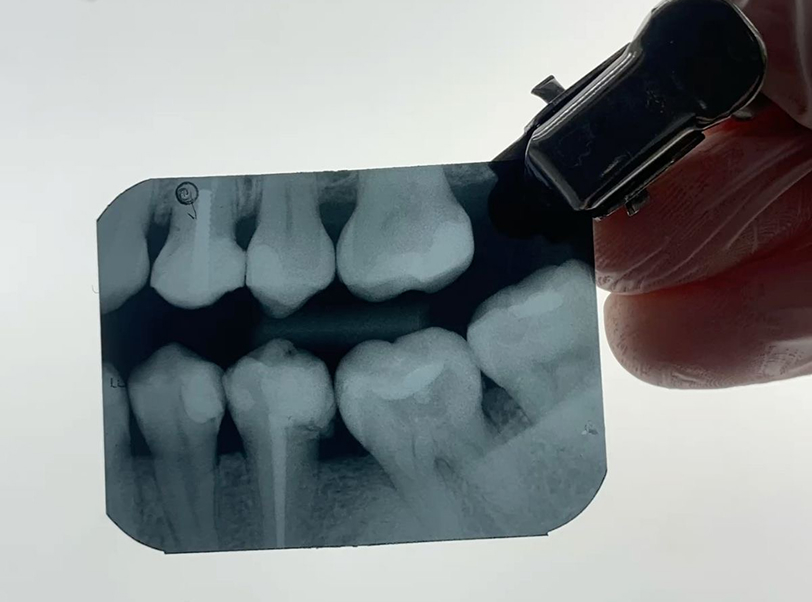

Realizamos a remoção de dentes inclusos, impactados ou mal posicionados, com técnicas minimamente invasivas que reduzem dor, edema e tempo de recuperação. Ideal para prevenção de infecções, desalinhamentos e complicações futuras.

Cirurgias auxiliares ao tratamento ortodôntico, como extrações de terceiros molares, caninos inclusos, tracionamento dentário e remoção de obstáculos ósseos. Atuação conjunta aos ortodontistas para acelerar e potencializar os resultados do alinhamento dentário.